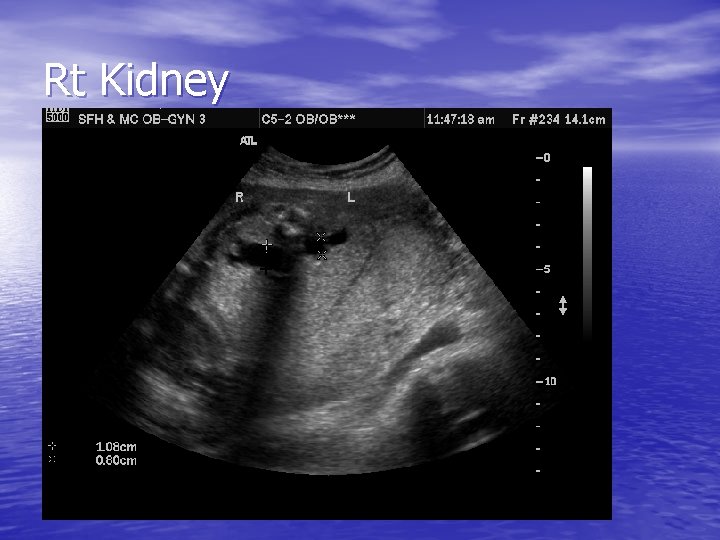

Rt Kidney

Right Kidney

WU – ultrasound cont • Long axis of the kidney is measured when evaluating underlying hydronephrosis • Kidneys which are large for gestational age and are less hyperechogenic – better prognosis • Kidneys which are hyperechogenic and are small have poorer prognosis due to advanced renal fibrosis